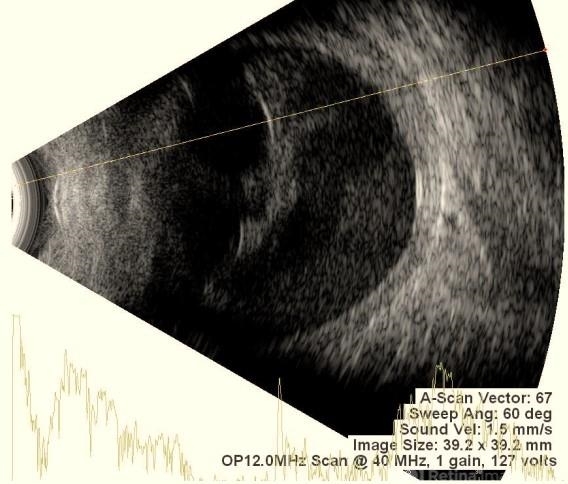

Retinal detachment

Retinal detachment on B-scan appears as a bright, V- or Y-shaped highly reflective membrane that moves independently with eye movement and remains tethered at the optic disc.